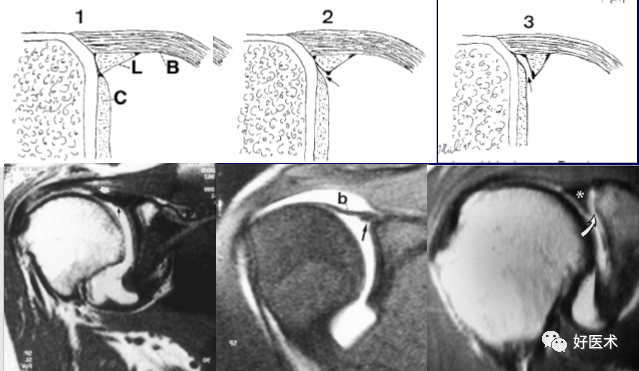

1.Bankart lesion

盂肱下韧带和前盂唇(前下盂唇韧带复合体)从关节盂边缘撕脱,伴肩胛骨骨膜的撕裂。首次损伤后不恰当愈合可导致反复肩关节不稳。

2.Bony Bankart lesion

前下盂唇韧带复合体从关节盂边缘撕脱,伴继发于前关节脱位的肩胛盂骨性骨折。

3.Perthes lesion

Bankart lesion的变异:前下盂唇韧带复合体从关节盂边缘脱离,但骨膜完整且向前内侧剥脱,因此盂唇可在正常解剖位置。

4.前盂唇韧带骨膜袖撕脱

多见于反复脱位的患者。类似于Bankart 损伤,但其肩胛骨前骨膜保持完整,MR 关节造影显示对比剂出现于盂唇与肩胛骨关节盂之间,而骨膜完整连于肩胛盂 。